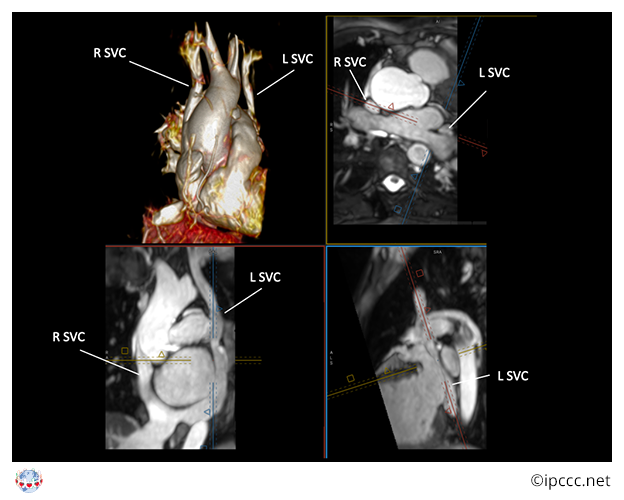

You are here: Left superior caval vein to coronary sinus ⇗ Left superior caval vein ⇗ Congenital anomaly of superior caval vein ⇗ Congenital anomaly of mediastinal systemic vein ⇗ Congenital anomaly of mediastinal vein ⇗ Structural developmental anomaly of heart or great vessels

A congenital cardiovascular malformation in which there is a left superior caval vein (superior vena cava) entering a left-sided coronary sinus.

Unless the code for absent right superior caval vein is used, this term assumes that a right superior caval vein is present and, therefore, there are bilateral superior caval veins with or without a bridging vein.